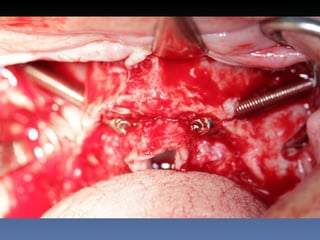

BOX 1 Sônia ElizabeteCorrea Idade – 58 anos Sexo – Feminino Raça – Caucasiana ASA – II Data- 27-04-2012 Diagnóstico: Desdentada total da maxila com atrofia severa Plano de tratamento: Reabilitação com 4 implantes Zigomáticos – “All-on-four Zigoma”.

Diagnóstico: Desdentada total da maxila com

atrofia severa

Plano de tratamento: Reabilitação com 4 implantes

Zigomáticos – “All-on-four Zigoma”.